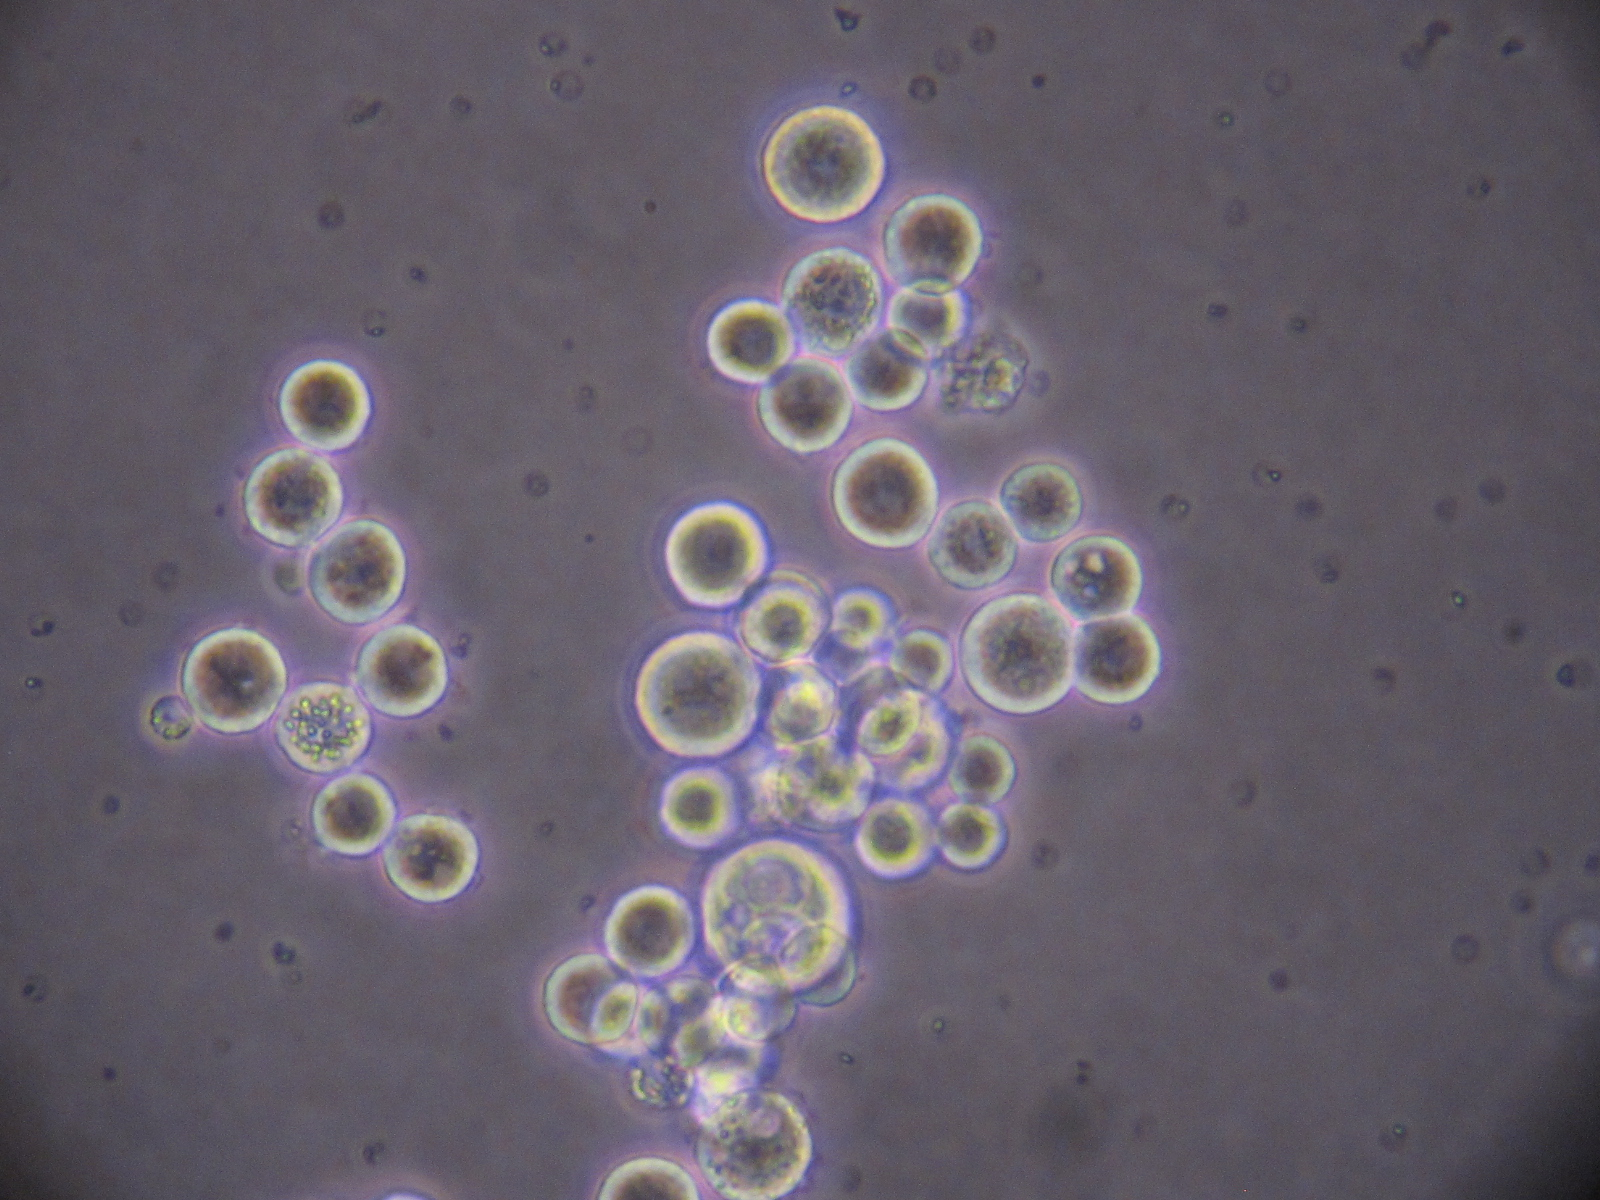

Distant metastasis is mostly initiated by tumor cells shed from the primary tumor into the blood circulation, known as circulating tumor cells (CTCs). Not all CTCs survive the harsh environment of circulation, but those that survive are carried to distant organs where metastatic tumors eventually arise. Advances in technologies have allowed us to be able to isolate CTCs from cancer patients. However, their biological properties which promote their survival and metastatic potential are still largely undefined. Our lab is interested in identifying the metastasis-initiating cells from the CTCs populations in patients and developing new therapeutic approaches for targeting them. The lab research focuses on two major topics: tumor intrinsic properties of CTCs that are capable of initiating metastasis and associated tumor extrinsic microenvironmental regulation which promotes this metastasis-initiating potential.

CTCs experience unique environmental stresses that could exhibit metastatic vulnerabilities. We combine transcriptional and epigenetic profiling with phenotypic investigations to elucidate the underlying mechanisms associated with context dependent role of nuclear receptors and signaling.

The hypoxia niche could impact metastatic capacity of the exited CTCs. We are investigating the long-term effect of hypoxia, termed “hypoxic memory”, and its associated molecular mechanisms as related to breast cancer metastasis.